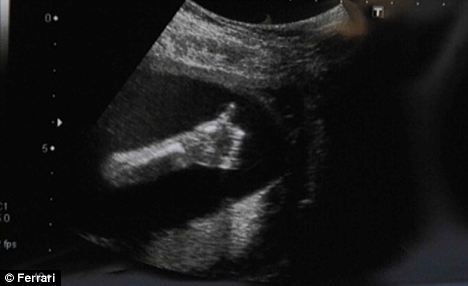

D i a n a в Юмор 15 лет Ок, мамуля! О детях Для будущих родителей наверное нет ничего приятнее, чем получить вот такой снимок УЗИ своего пока еще нерожденного малыша Источник Посмотрите еще 20 записей на эту тему Отменить Ответить эх, детки)) про маршрутку Чаты Беременных Выберите чат: Январята-2026 Февралята-2026 Мартята-2026 Апрелята-2026 Майчата-2026 Июнята-2026 Июлята-2026 Августята-2026